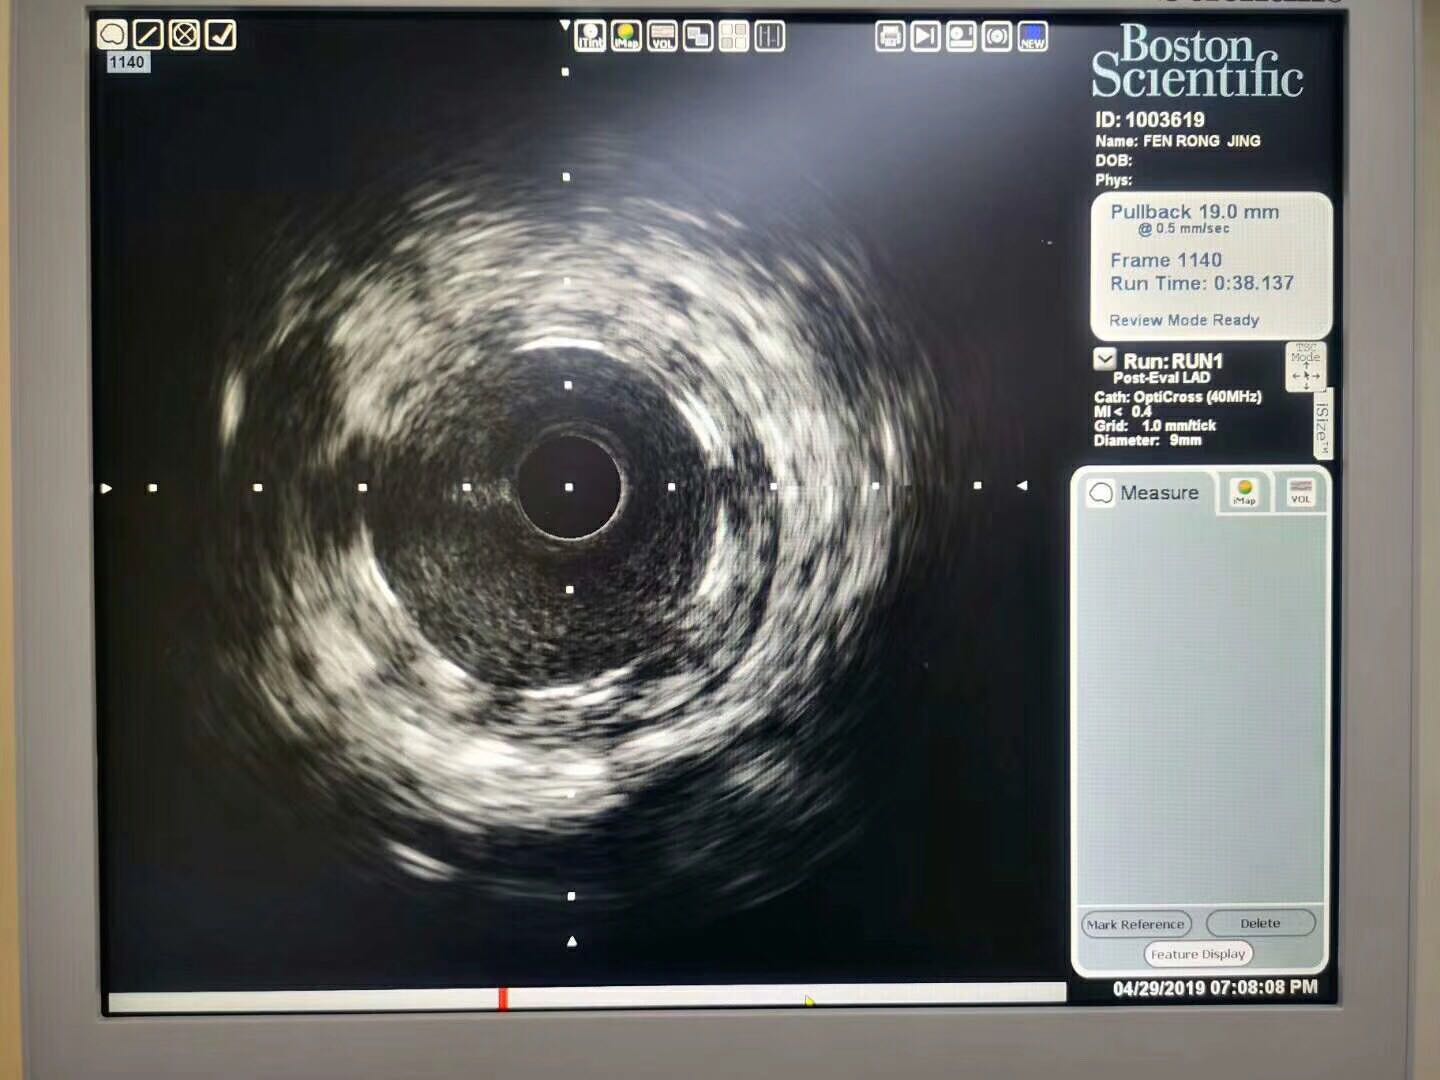

该患者为女性,年龄64岁,患者因“不稳定性心绞痛”多次就诊,饱受病痛折磨。本次就诊我院后,完善冠状动脉造影示LAD近段80%重度狭窄,在副院长白锋带领下,治疗团队严格把握适应症,和患者反复沟通后,最终于病变处成功植入3.5*21mmNeoVas生物可吸收支架,手术准备充分,术中严格执行PSP技术,术后经IVUS证实支架释放完美。生物可吸收支架是目前全球的研究热点,给冠心病患者治疗带来了新希望,避免金属植入物永存体内,恢复血管舒缩功能,避免金属牢笼禁锢,利于再次介入治疗,实现从“血管再通”到“血管再造”的新蜕变。